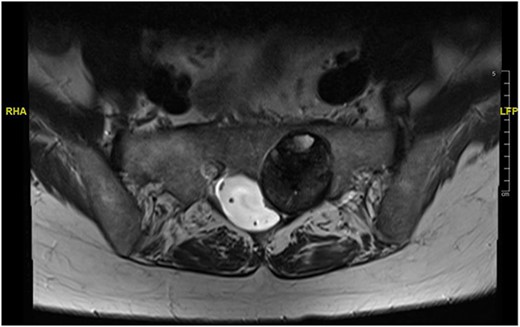

At a further review (November 2018), a contrast MRI scan was requested at a follow-up in early November for 3 months post-index scan. At the follow-up, a left S1/S2 sacral tumour (most possibly schwannoma) with no change in the size was diagnosed. Repeat physical examination confirmed status quo on the neurological deficit. The decision was to review after 12 months as the patient remained stable.

Reviews in July 2019 (with an MRI scan in December 2019) and December 2020 confirmed no neurological deterioration but some increased back and leg pain when standing for some time. A repeat MRI scan confirmed an increase in the size of the lesion (Figs 1 and 2). A biopsy was arranged with a plan for a follow-up surgery. Results of the CT-guided biopsy indicated a diagnosis of metastatic malignant melanoma. Discussions with the patient did not localise any skin lesion responsible for the metastatic deposit, an F18-fluorodeoxyglucose positron emission tomography (18F-FDG PET/CT) scan and a conventional computed axial tomography (CT) scan was organised (April 2021), which revealed sacral destruction and no other deposits in the chest, abdomen and pelvis (Figs 3 and 4). Our patient had a reported SUV of 3.6, indicating a malignant lesion that was then confirmed operatively.